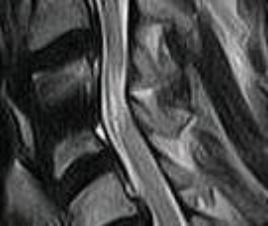

| 2007年12月13日MRI画像(術後4年半) |

術後4年半検診のMRIです

明らかに神経は広がっていますが、多少後方の

出っぱりが気になります。

先生のお話ではこの後方は問題あいということです

ただ、内部の白くにごった部分が今年の二月にくらべて

多少濃くなってしまっているようで、これは明らかに

日ごろのくせや、不摂生が原因だろうと思いました。